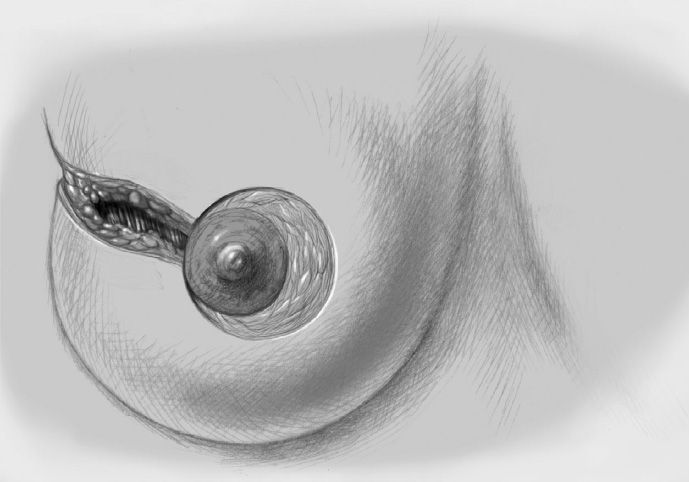

The basic decision on whether to use a complex oncoplastic technique is made when the skin is marked preoperatively, with the patient standing or sitting upright. Many surgeons successfully combine the B-plasty incision with periareolar de-epithelialization and excision of a straight or curved ellipse of peripheral skin (Chapter 1.3). When marking the periareolar deepithelialization pattern, an eccentric incision may be necessary to adjust the repositioning of the nipple–areola complex to the anticipated volume displacement.

The skin is incised superficially along the preoperative mark, initially with a scalpel. Many surgeons then proceed using electrocautery needle or scissors.

The periareolar skin is de-epithelialized. Here, too, there are various options. A strip of the most superficial skin layer can be excised with dissecting scissors applied flat or with a scalpel. It is important not to leave behind any surface containing squamous epithelium, but on the other hand the dermis and the important vascular layer beneath it must not be injured. The purpose of periareolar de-epithelialization is to recenter the nipple–areola complex and also to tailor excess skin to the new breast shape following extensive tumor resection.

Segmental excision of the area containing the tumor with resection margins as wide as possible to meet oncological criteria. Oncoplastic techniques should be used to achieve maximal oncological safety and avoid subsequent further resection.

Further resection is performed if necessary to ensure R0 status.

The former tumor region is marked with clips.

To cover the defect, the glandular lobes are mobilized from the adjacent parenchyma after subcutaneous dissection. The principle of intramammary lobe creation is to mobilize large parts of the breast (> 25%) either relative to the skin or relative to the pectoralis muscle. This “liberation” of the breast from one of its two planes of fixation allows adequate dissection and rotation of sufficient breast tissue. The Y-flap and rotation flap shown in Chapter 3.2.1 are examples of intramammary dissection.

When the breast is mobilized subcutaneously, it must be ensured that both the dissected skin layer and the breast tissue are sufficiently thick. For the layer of breast tissue, a minimum thickness of 1 cm is desirable. The ratio of base to length must also be considered.

The former tumor bed is marked with clips for optimized postoperative radiotherapy.

A Redon drain is placed prior to approximation of the breast lobes.

The mobilized breast lobes are rotated into the defect and approximated by interrupted sutures. Complete covering of the defect is desirable.

The skin is closed in two layers with recentering of the nipple–areola complex using interrupted sutures (Vicryl 3–0) according to the preoperative de-epithelialization pattern, which can be corrected at this time.

The skin is closed with an intracutaneous continuous monofilament suture.

Special Technique Complex Oncoplastic Breast-Conserving Surgery